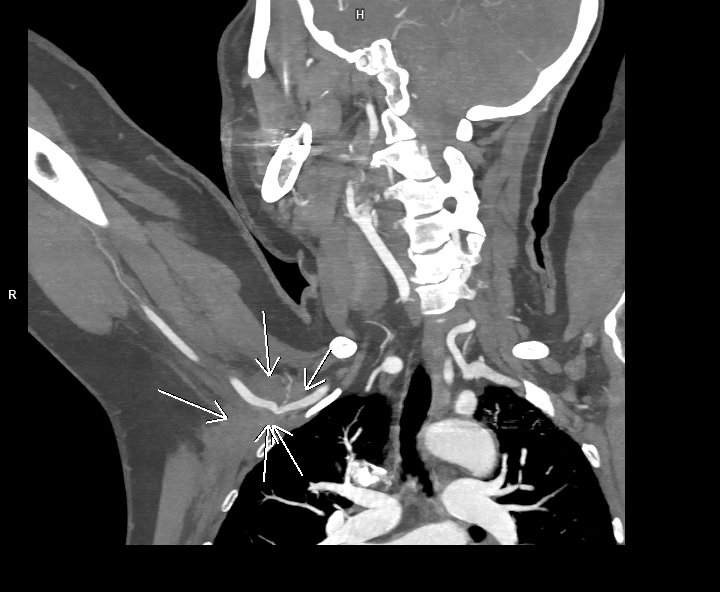

Discuţie caz nr 40: pacienta cunoscută cu neoplasm mamar este trimisă la examinare angioCT pentru suspiciune ecografică de tromboză de venă axilară dreapta. Se evidențiază o leziune expansivă densă cu priză de contrast în timp venos situată în vârful axilei drept care invadează pachetul vascular axilar determinând reducere de calibru a arterei axilare drepte și ocluzia venei axilare drepte cu dezvoltare de circulație colaterală de tip venos  la nivelul țesutului subcutanat al hemitoracelui drept și în musculatura paravertebrala posterioară.